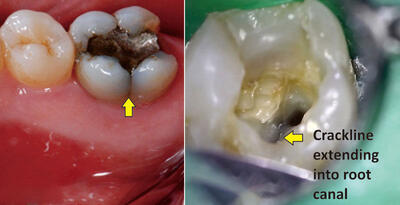

عصب کشی دندان

عصب کشی دندان چگونه است؟

عصب کشی دندان چیست؟ هرآنچه باید قبل از نشستن روی صندلی دندانپزشک بدانید

تا چند روز بعد از عصب کشی دندان درد دارد

تا چند روز بعد از عصب کشی دندان درد دارد

عصبکشی: راهی برای ترمیم ساختار دندان

در این مقاله، به بررسی فرآیند عصبکشی میپردازیم تا شما را با اهمیت و روشهای این رویکرد پزشکی آشنا کنیم. همراه ما باشید تا به دنیایی از سلامت و لبخند زیبا سفر کنیم.